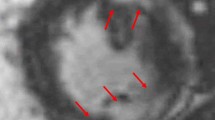

Cardiac magnetic resonance imaging with gadolinium and 18F-fluorodeoxyglucose-positron emission tomography at time of diagnosis and during follow-up. Advanced imaging for a Patient 1 shows i cardiac magnetic resonance imaging reported in the clinical setting as within normal limits. Re-review for the purposes of publication found the scan was of insufficient quality to accurately detect presence of delayed enhancement. ii 18F-fluorodeoxyglucose-positron emission tomography at time of presentation demonstrates abnormal heterogeneous and moderate-to-markedly increased metabolism in hilar and mediastinal nodes consistent with cardiac sarcoidosis, as well as cardiomegaly and diffuse uptake in both ventricles and the right atrium. iii Progress 18F-fluorodeoxyglucose-positron emission tomography following 3 months’ treatment with prednisone and methotrexate demonstrates response to treatment with a reduction in the size and metabolism of the hilar and mediastinal lymph nodes. In addition, the heart is smaller and the increased uptake seen in the right ventricle and the right atrium on the initial scan has resolved, although there is persistent metabolism in the septum. iv Progress 18F-fluorodeoxyglucose-positron emission tomography following 17 months of immunosuppression demonstrates response to treatment with complete resolution of abnormal metabolism in the myocardium, but persisting areas of avidity in the mediastinal and hilar lymph nodes. b Patient 2 shows i cardiac magnetic resonance imaging with no abnormalities detected at presentation. ii 18F-fluorodeoxyglucose-positron emission tomography at time of presentation demonstrates abnormal active sites of focal myocardial inflammation in the basal anteroseptum, basal septum, and inferior walls that was consistent with cardiac sarcoidosis. iii Progress 18F-fluorodeoxyglucose-positron emission tomography following 6 months of immunosuppression with prednisone and methotrexate demonstrates resolution of previously abnormal focal increased 18F-fluorodeoxyglucose accumulation in the left ventricle consistent with resolution of areas of inflammation

Biochemical investigations including serum ACE of 24 (8 to 64), 1,25 vitamin D of 99 (60 to 100), and urine calcium of 6.6 nmol/L were all within normal limits. Dermatology and Ophthalmology review found no evidence of cutaneous or ocular sarcoidosis. A second CMR found normal biventricular size and systolic function and no late GAD enhancement seen in LV to suggest sarcoid involvement (Fig. 1bi). For the purposes of publication, the second CMR was subsequently reviewed by the same third party with specific expertise as used in Case 1. There was agreement that this CMR was within normal limits.

She proceeded to cardiac FDG-PET due to high clinical suspicion of CS despite two CMR scans within normal limits. Her BSL prior to scanning was 6.6 mmol/L following a 12-hour fast. The FDG-PET scan was suggestive of CS with active sites of focal myocardial inflammation in the basal anteroseptum, basal septum, and inferior walls (Fig. 1bii). She underwent successful permanent pacemaker (PPM)-AICD insertion due to risk of future VT and sudden cardiac death, and was commenced on metoprolol. She was commenced on prednisone 1 mg/kg orally administered daily and methotrexate. She was discharged and has had no further cardiac events. A repeat cardiac FDG-PET at 6 months demonstrated resolution of previously abnormal focal increased FDG accumulation in the LV consistent with resolution of areas of inflammation (see Fig. 1biii). The salient features of the two presented cases are shown in Table 3.